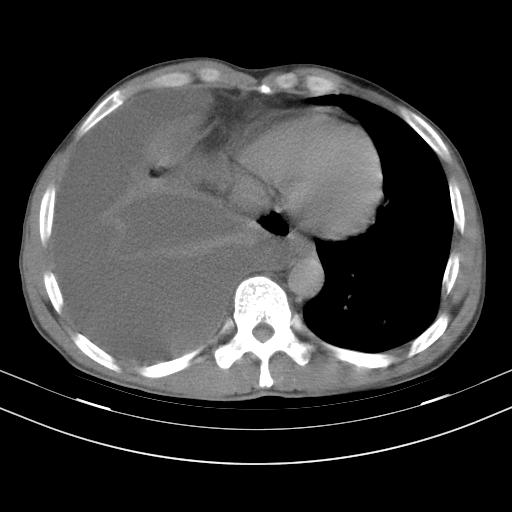

男性,44岁,结核病史多年。现胸闷气短,咳嗽,偶咳血。

1、右侧大量胸腔积液伴右肺压缩性膨胀不全,建议抽液治疗后复查 2、两肺继发性tb伴空洞形成。

1)两肺继发性肺结核伴空洞形成,左肺多发性结核球。2)右侧大量胸腔积液伴右肺部分膨胀不全。3)纵隔淋巴结肿大。

1,双肺多发结节 并空洞影改变, 左侧胸腔积液并部分包裹, 结合原病史首先考虑结核. 但也不除外其它.

2,左侧有一根肋骨陈旧性骨折? 建议追查 .